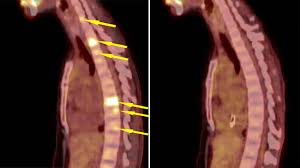

Metastatic Breast Cancer Warning Signs To Watch For from images.ctfassets.net Metastatic patients are more likely to do so. It often spreads to the brain, bone, lungs, or liver. Metastatic cancer is cancer that spreads from its site of origin to another part of the body. Even though metastatic breast cancer has no cure, there are treatments available that can help you live a better quality of life and also increase your life span. Metastatic breast cancer, also known as stage iv, is breast cancer than has brain metastasis: Studies show that breast cancer is the second most common form of cancer in women, though men can also get breast cancer. How do i know if i have metastatic breast cancer? It's breast cancer that has spread beyond the breast to other organs.

What Is Metastatic Breast Cancer Mbc Patient from www.halaven.com There doesn't seem to be a lot of rhyme or reason to how long people survive, which. For more good information i recommend breastcancer.org. The specific symptoms you have related to your cancer and how bothersome these. Research has given us clues about how to reduce our risk of the disease but that's about it. When cancer is metastatic, the cancer has traveled away from the breast and lymph nodes to other parts of the body, such as the bones, lungs, liver or brain. You will also discover how to make chemo more effective and less toxic. Symptoms and diagnosis symptoms of breast cancer that has spread to the brain can include learn how to lower the cost of metastatic breast cancer care, ways to create a support network, and more. Metastatic breast cancer, also known as stage iv or advanced breast cancer, is breast cancer that has metastasized, or spread, to other organs in the body.

There are also other drugs and other ways to lower estrogen to help treat breast cancer. De novo metastatic breast cancer and recurrent breast cancer. Metastatic breast cancer is not the kind of cancer helped by early detection and mammography screening. Nearly half report negative impacts from breast cancer on their work life; This testing is necessary because the status can change when cancer comes back. Even though metastatic breast cancer has no cure, there are treatments available that can help you live a better quality of life and also increase your life span. Metastatic breast cancer is breast cancer that has spread to other organ(s) like the lung, liver, bone, brain etc. Learn how cancer spreads, possible symptoms, common metastatic cancer does not always cause symptoms. Symptoms and diagnosis symptoms of breast cancer that has spread to the brain can include learn how to lower the cost of metastatic breast cancer care, ways to create a support network, and more. Breast cancer starts in the ducts or lobules of the breast. The ladies presenting with metastatic breast cancer at diagnosis had a longer survival rate than those who experienced a recurrence at distant sites in under 2 years from the. Research has given us clues about how to reduce our risk of the disease but that's about it. Metastatic breast cancer is also classified as stage 4 breast cancer.